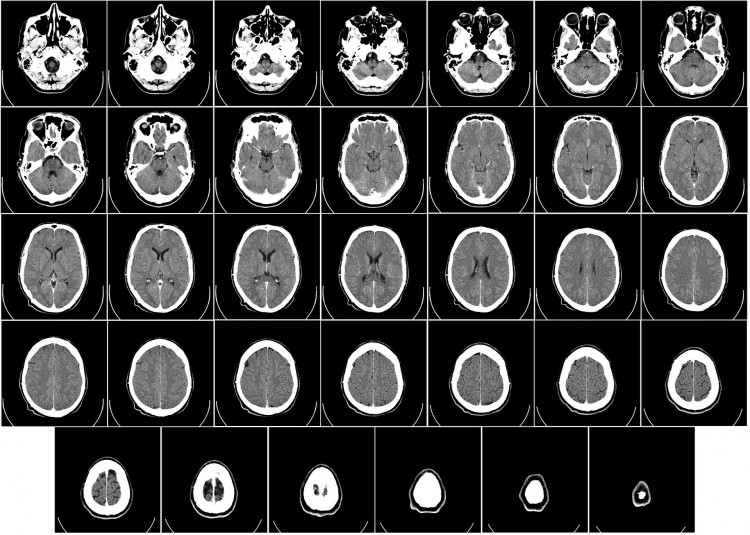

Radiation therapists administer radiation treatment to help fight cancer, including monitoring patients’ progress and reporting this data to the proper medical professionals. They help patients to understand how radiation therapy works by providing explanation and answering questions. They must have the ability to perform X-rays, operate a variety of medical equipment, and report any equipment malfunctions.